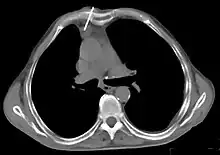

Scanner thoracique

Le scanner thoracique est plus précis que la radiographie thoracique dans le diagnostic des thymomes, en raison d'une plus grande sensibilité envers les masses médiastinales. L'injection de produit de contraste iodé n'est pas forcément nécessaire, mais permet de préciser les rapports du thymome avec les structures vasculaires. Ceci permet à la fois la stadification et de préciser la stratégie chirurgicale lorsqu'elle est envisagée[28].

Les thymomes se présentent comme une masse bien définie du médiastin antérieur, proche du péricarde et dans un plan plus antérieur que les gros vaisseaux intrathoraciques (aorte ascendante et sa crosse, artère pulmonaire, veine cave supérieure). La masse peut être sphérique ou lobulée, mais présente un aspect homogène (plus rarement kystique) qui se réhausse après injection et peut contenir des calcifications[29].

Présentation tomodensitométrique classique d'un thymome à un stade précoce (cercle rouge). À l'arrière, l'aorte, la veine cave supérieure et l'artère pulmonaire sont visibles en coupe.